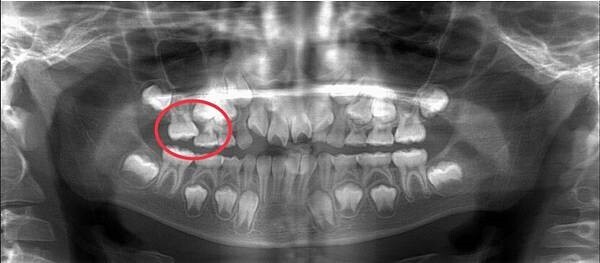

第四種是異位萌發,例如恆牙萌發角度異常,頂到前方的乳牙牙根,導致乳牙牙根提早吸收、鬆脫,造成日後齒列排列不整。

恆牙萌發角度異常,恐影響日後恆牙齒列整齊